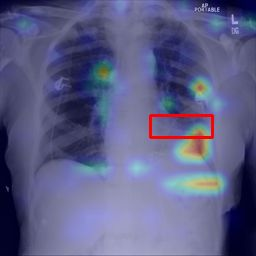

Deployments of artificial intelligence in medical diagnostics mandate not just accuracy and efficacy but also trust, emphasizing the need for explainability in machine decisions. The recent trend in automated medical image diagnostics leans towards the deployment of Transformer-based architectures, credited to their impressive capabilities. Since the self-attention feature of transformers contributes towards identifying crucial regions during the classification process, they enhance the trustability of the methods. However, the complex intricacies of these attention mechanisms may fall short of effectively pinpointing the regions of interest directly influencing AI decisions. Our research endeavors to innovate a unique attention block that underscores the correlation between 'regions' rather than 'pixels'. To address this challenge, we introduce an innovative system grounded in prototype learning, featuring an advanced self-attention mechanism that goes beyond conventional ad-hoc visual explanation techniques by offering comprehensible visual insights. A combined quantitative and qualitative methodological approach was used to demonstrate the effectiveness of the proposed method on the large-scale NIH chest X-ray dataset. Experimental results showed that our proposed method offers a promising direction for explainability, which can lead to the development of more trustable systems, which can facilitate easier and rapid adoption of such technology into routine clinics. The code is available at www.github.com/NUBagcilab/r2r_proto.